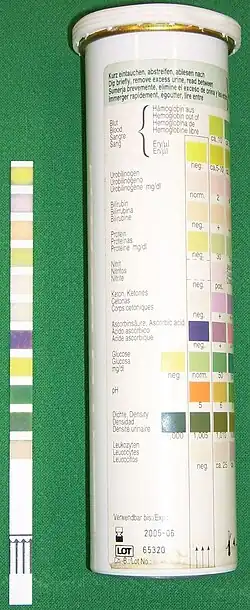

Neben der Erhebung der Anamnese und der körperlichen Untersuchung steht die Urindiagnostik an erster Stelle. Hierzu wird „sauberer Mittelstrahlurin“ genommen, d. h. die erste Urinportion wird verworfen, genauso wie die letzte. Außerdem sollte man beachten, dass man nur 10 ml Urin abnimmt, denn mehr ist zur Diagnostik nicht nötig. Wichtig ist, dass das Genitale vorher gründlich gesäubert wird, damit eine Verunreinigung des Urins mit der normalen Schleimhautflora, mit Fluor vaginalis o. ä. vermieden wird. Des Weiteren muss bei der Frau darauf geachtet werden, dass die richtige Technik angewandt wird, was bedeutet, dass die Schamlippen gespreizt werden, damit der Urin nur wenig Kontakt mit der Umgebung bekommt.

Es ist auch möglich, den Urin mittels Einmalkatheterisierung oder durch eine suprapubische Blasenpunktion zu gewinnen. Ein erster Test erfolgt mit sogenannten Urinteststreifen. Der Streifen dient dem Nachweis von roten Blutkörperchen, weißen Blutkörperchen und Nitrit. Nitrit wird von vielen der infektverursachenden Bakterien (zum Beispiel auch Escherichia coli) aus Nahrungsnitrat gebildet. In einem weiteren Schritt wird der Urin mikroskopisch untersucht. Hierbei können die oben genannten Zellen sowie Bakterien und Kristalle identifiziert werden. In einem letzten Schritt erfolgt das Anlegen einer Urinkultur zur genauen Differenzierung des Erregers. Diese dient weiterhin der Bestimmung der Keimzahl (eine Harnwegsinfektion ist ab etwa 105 KbE pro Milliliter wahrscheinlich) und Erstellung eines Antibiogramms, um damit gegebenenfalls eine gezielte Antibiotikatherapie zu ermöglichen.